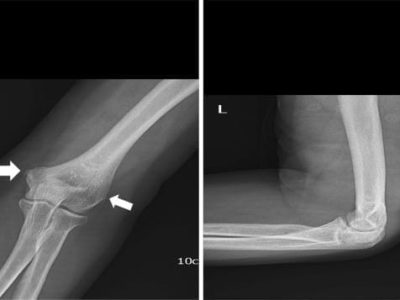

What are Radial Head and Neck Fractures? Radial head and neck fractures are the most common type of elbow fractures in adults, accounting for 33% of all elbow fractures. These fractures can happen on their own or alongside other bone,…